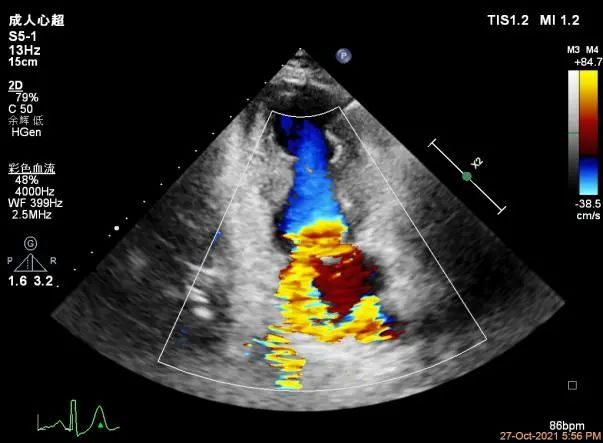

3D-color MV view:血流主要来源于A2区,少部分来源于A1区

Color-view:返流束主要来源于2区脱垂

3D-color:残余少量返流

(1)本例患者为DMR,可见明显的A1和A2区脱垂,究竟应该夹合哪个位置?如果选择脱垂最重的位置A1/P1区,将面临后瓣Tething的改变,瓣叶长度不够。所幸通过二维和三维的Color发现主要的Jet来源于A2区域,因此首次夹合位置应该确定为返流最重的A2区域略偏A1区,此处后瓣长度很理想。